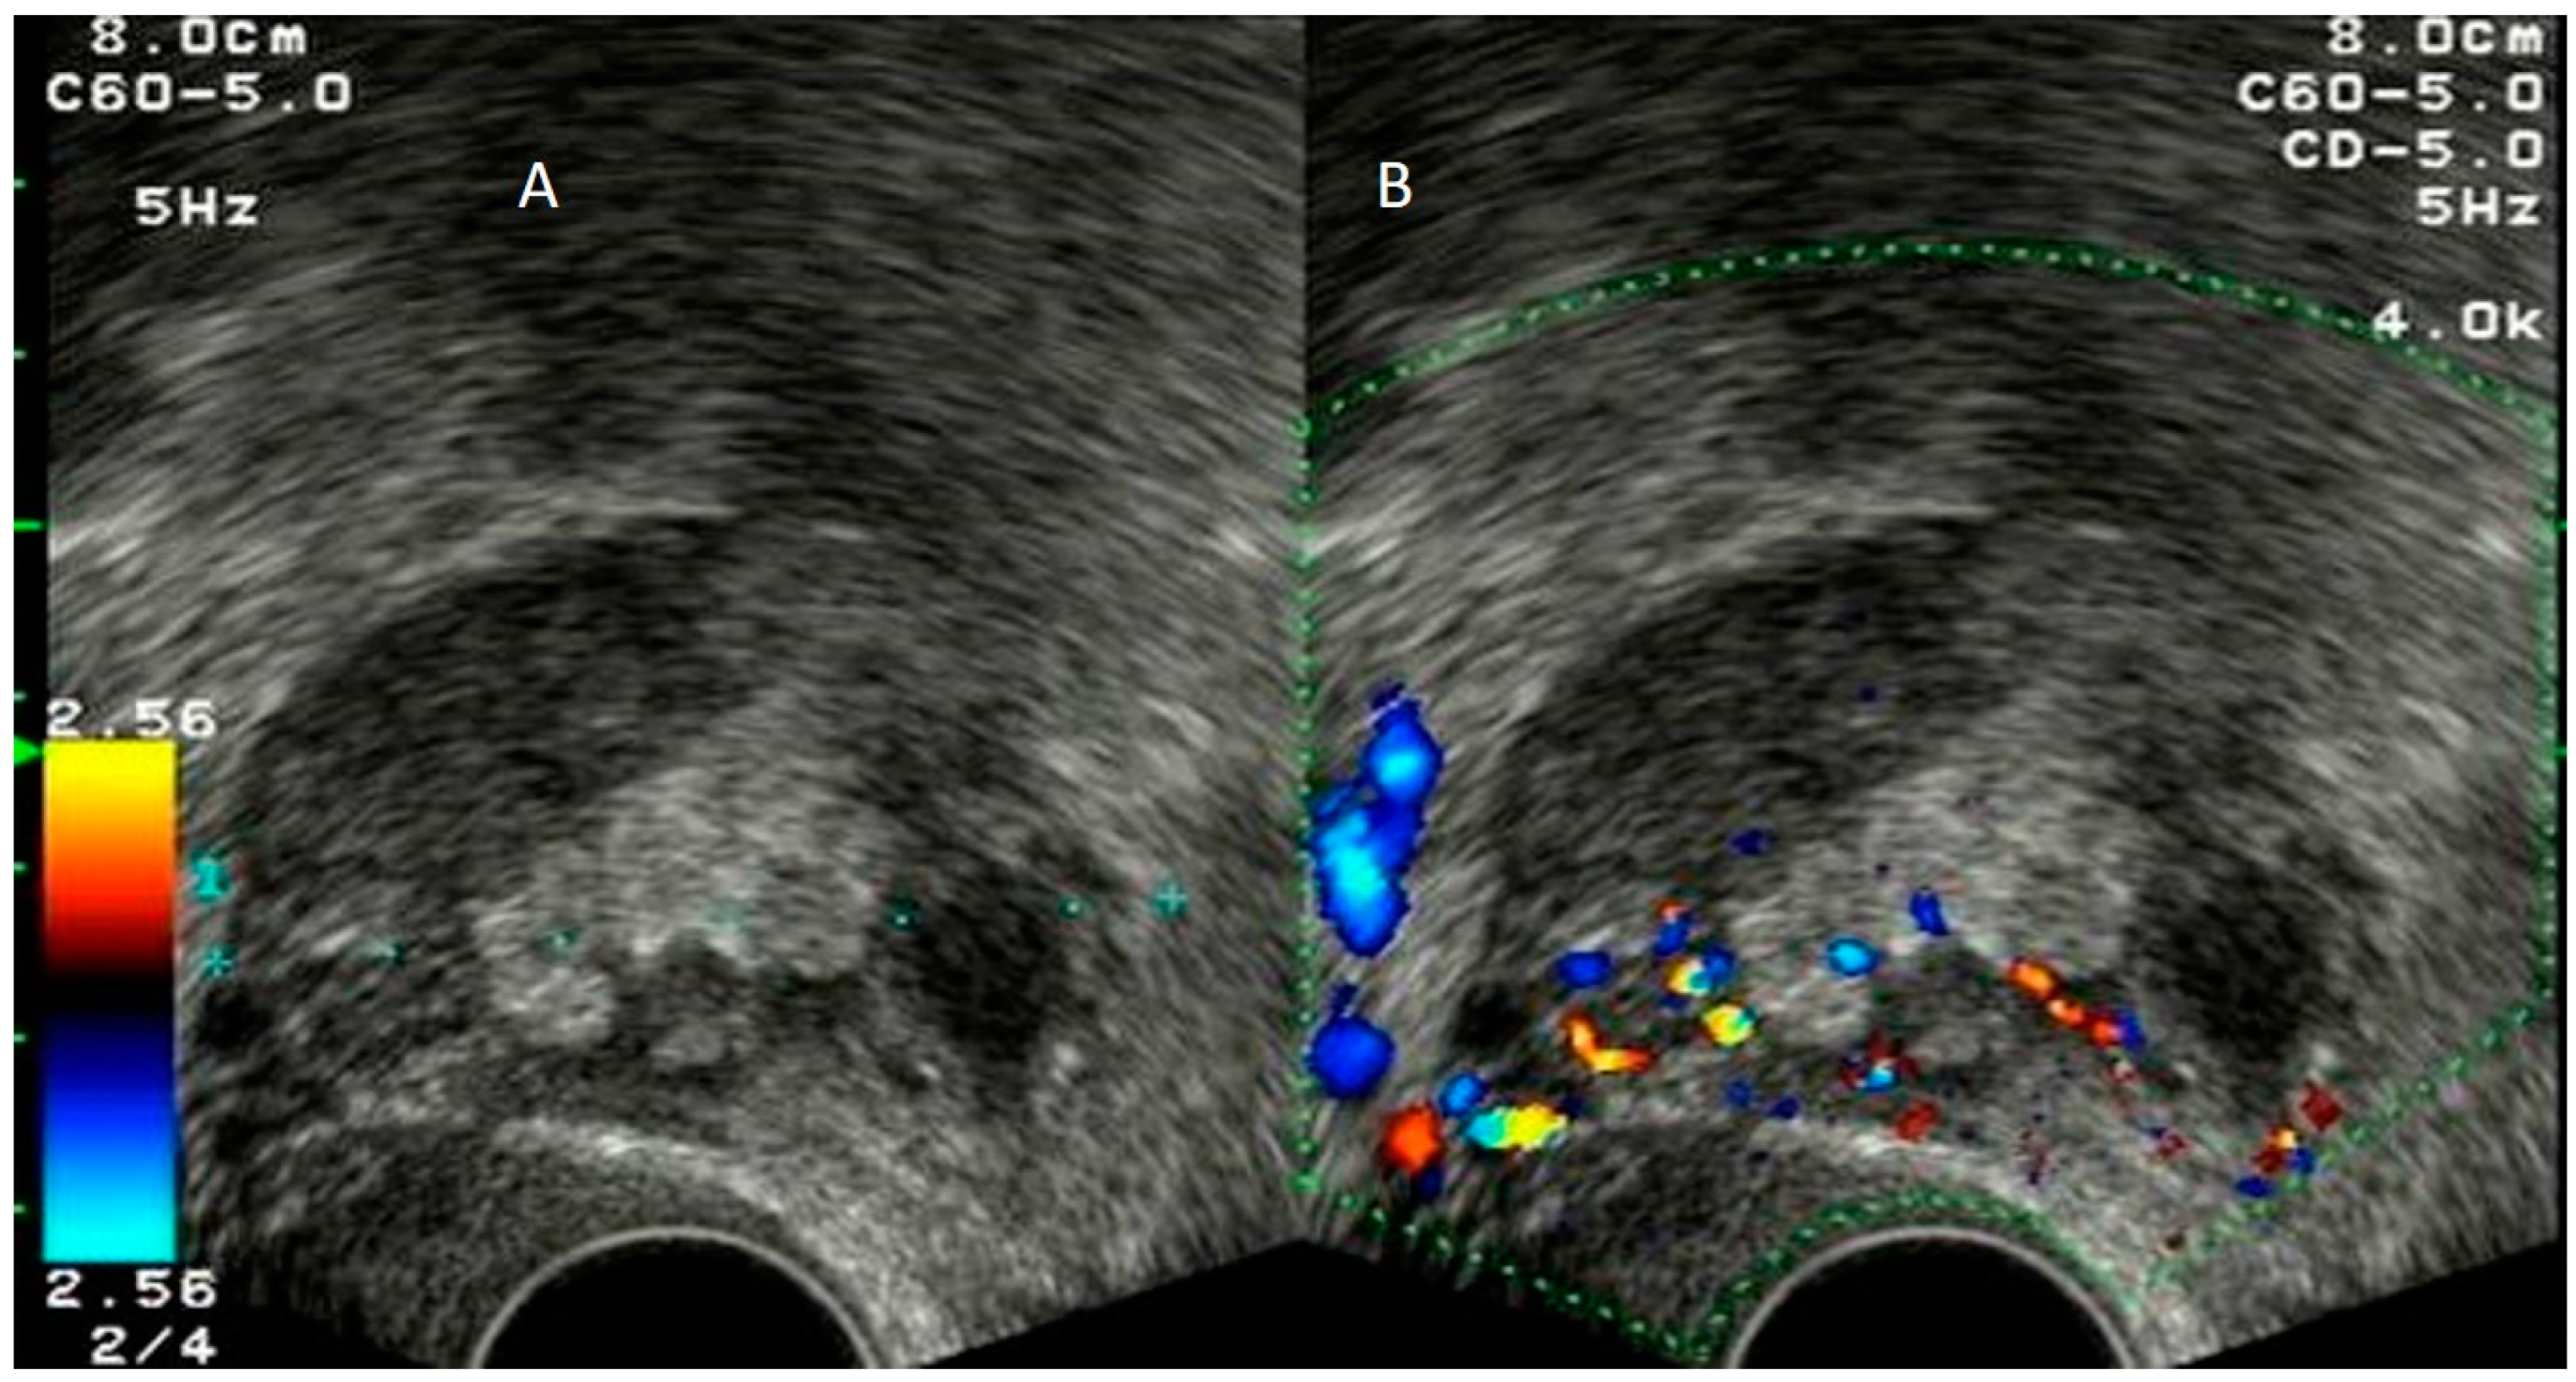

4.1. Pelvic Congestion